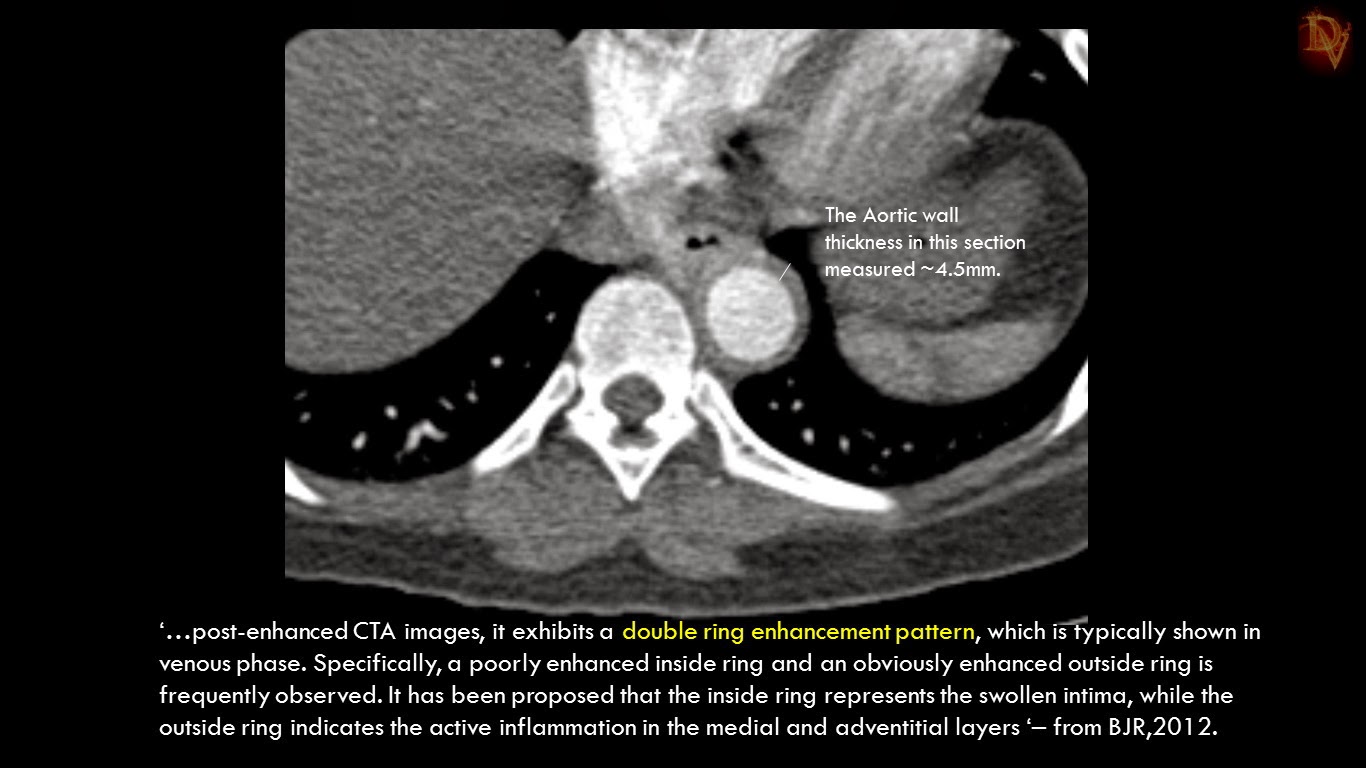

Ultimate Radiology TAKAYASU ARTERITIS A less common presentation Ring Enhancement Radiology The enhancing lesions show different patterns of enhancement: 1a, 1b) and mri show a well circumscribed, ring enhancing brain lesion, of approximately 4cm in diameter, in the left. Magic dr or dr magic. The lesions are also located. The most common radiological abnormality seen in young indian patients with epilepsy is single small enhancing (ring/disc) computed. Many features of the. Ring Enhancement Radiology.